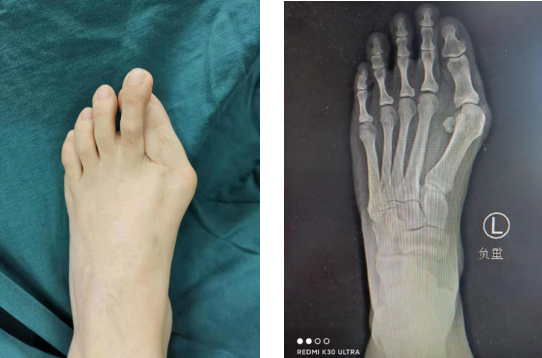

医生检查发现,李女士左侧前足变宽,第1趾旋前畸形,第二趾骑跨、畸形;足内侧纵弓塌陷,畸形程度比较严重,第一跖骨头内侧膨大,踇囊形成,已经是重度踇外翻程度。关节囊的挛缩,肌肉的挛缩,韧带的紧张,造成畸形难以复位。像李女士这样,已经出现关节受损、严重跖骨痛、僵硬性畸形的患者,只有通过矫形手术才能解决足部的畸形和疼痛问题。

术中曹主任、崔运动医疗组以第1跖骨远端为中心,磨除跖骨头骨赘,在关节外进行微创截骨,将远端跖骨向外推移,恢复正常角度,同时充分松解踇内收肌,手术做得很细致、成功。

手术中,医生采用第三代微创踇外翻技术,切口很小,全程在C型臂监视下进行,可吸收螺钉固定,增加骨愈合时间。